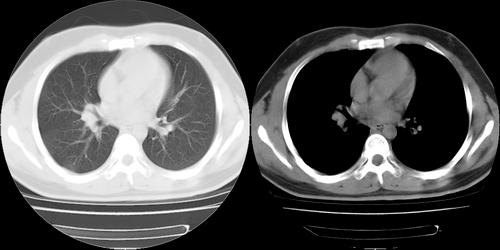

患者 男性 25岁,体检觉得右肺门感觉增大,请会诊,有没有异常?(我科诊断:未见异常)

右肺门增大,囊状影与肺动脉分支有关,上叶支气管受压移位。

考虑发生于右肺动脉分支的肺动脉瘤。

应该是主肺动脉,随然略扩张,但够不上动脉瘤。此病理正常

建议增强,右肺上叶前段支气管受压变细,腔静脉后方见肿大淋巴结.考虑结节病或肺门占位.

应该是右肺动脉影,要明确则做个增强扫描。

平扫未见异常,右肺门的改变我也认为是正常的,若不放心就作局部强化扫描。